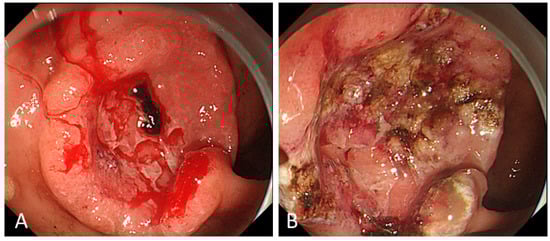

2. Endoscopic Management for Bleeding from Unresectable GC

2.3. Modalities of ET